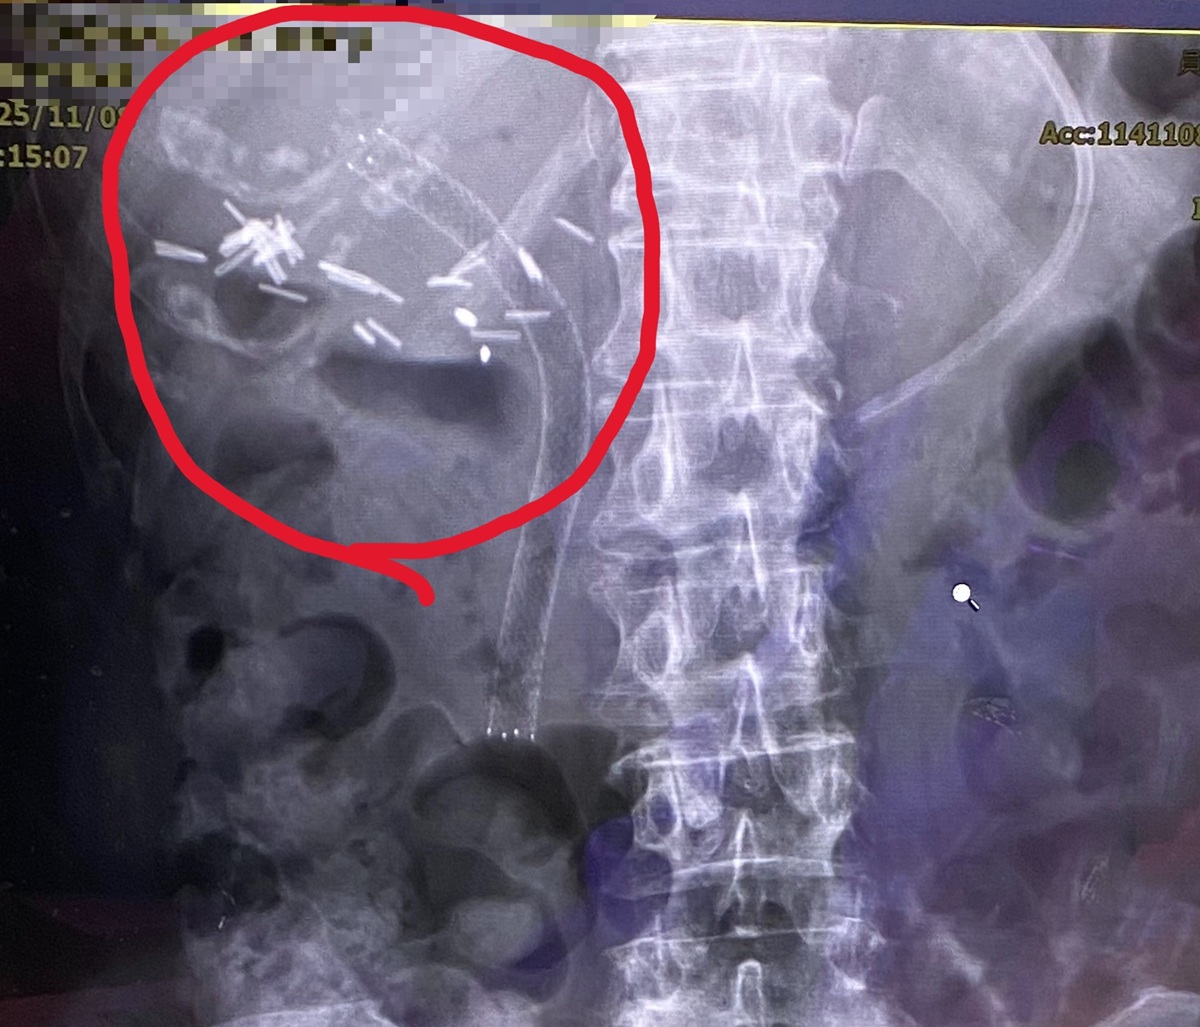

經由逆行性胰膽管鏡檢查發現,原有塑膠支架已完全被膽汁阻塞,使肝內膽管擴張。手術團隊以精準技術使導管通過狹窄處先移除塑膠支架後,再置放金屬膽道支架,讓膽汁得以順利排出。術後X光影像顯示,金屬支架位置良好,膽汁引流恢復正常。患者術後症狀明顯改善,包括腹痛、噁心及黃疸皆逐步消退,肝功能指數亦恢復正常。

▲曾醫師指出,膽道支架依材質區分為塑膠與金屬兩類,適應症及使用期限不同。(圖/員榮醫院提供)

▲曾醫師指出,膽道支架依材質區分為塑膠與金屬兩類,適應症及使用期限不同。(圖/員榮醫院提供)